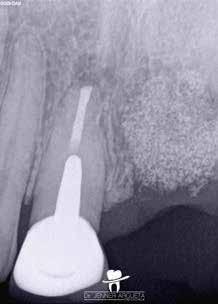

Egy 38 éves nőbeteg a korábban kezelt jobb felső második kisőrlőfogából (1.5) kiinduló mérsékelt fájdalom miatt jelentkezett rendelésünkön. A kórtörténetében jelen panasza szempontjából releváns információ nem szerepelt. A beteg a klinikai vizsgálat során vertikális kopogtatásra enyhe érzékenységet jelzett. A kérdéses fog körül mérhető szondázási mélység és a fogmobilitás fiziológiás volt. Periapicalis röntgenfelvételen egy, a fog gyökércsúcsán túl presszálódott betört gyökérkezelő műszerből származó eszközfragmentumot láttunk (2. a. ábra). A preoperatív CBCT-felvétel a buccalis csontlemez épségét igazolta (2. b-c. ábra). A fog revíziója öt hónappal korábban történt. A már előzőleg gyökérkezelt, gyökértömött, majd revideált 1.5-ös fog esetében a diagnózisunk periodontitis periapicalis symptomatica volt. A periapikális elváltozás kezelése érdekében navigált endodonciai mikrosebészeti beavatkozást végeztünk.

A felső állcsontról intraorális szkent (TRIOS) készítettünk, és az ezáltal kapott STL fájlt (2. d. ábra) a CBCT-felvétel során nyert DICOM fájlokkal a Zirkonzahn.Implant-Planner (Zirkonzahn) szoftverben egyesítettük. A sebészi sablont ebben a programban megterveztük, majd a Meshmixer (Autodesk) szoftver se-

gítségével tovább módosítottuk. Az így kapott sebészi sablon egyértelműen meghatározta a periapikális terület eléréséhez szükséges csontablak határait (2. e-f. ábra) Helyi érzéstelenítést követően teljes vastagságú mucoperiostealis lebenyt képeztünk, majd a buccalis csont feltárását követően (2. g. ábra) a sablon segítségével bejelöltük a preparálandó csontablak határait (2. h. ábra). A csontablak kialakítása során Piezotome CUBE LED kézi-darabot alkalmaztunk, majd a leemelését követően a betört eszközt megkerestük (2. i. ábra) és eltávolítottuk (2. j. ábra). A rezekciót ultrahangos megmunkáló fejekkel (ACTEON) végeztük, majd retrográd preparáció következett.

A retrográd gyökértömés elkészítése során TotalFill BC RRM Fast Set Putty-t (FKG) használtunk (2. k. ábra). A lebeny széleit 5/0-s Prolene varratokkal egyesítettük (2. l. ábra). A varratok a műtétet követően 72 órával kerültek eltávolításra. A beteg két évvel később kontrollröntgen készítése céljából érkezett rendelőnkbe. A vizsgálat során a fog tünetmentesnek és funkcióképesnek bizonyult (2. m. ábra).